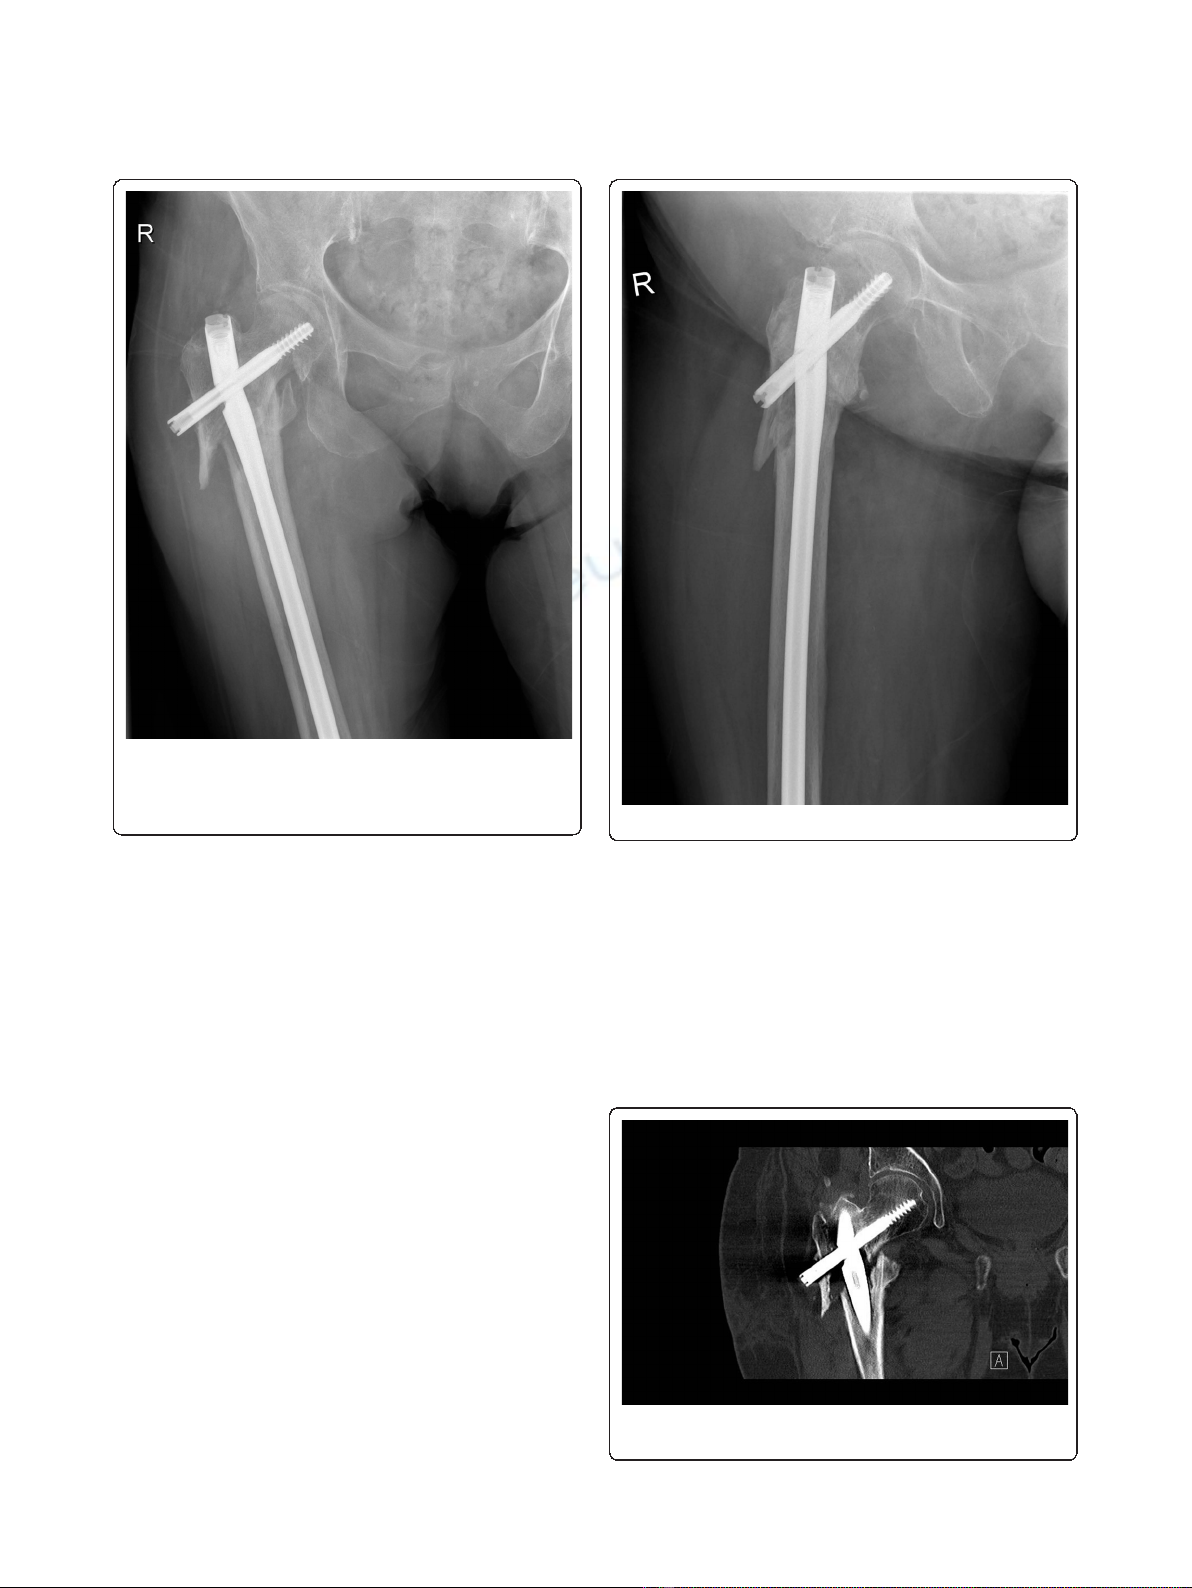

RIA protocol (Figure 7). Reduction forceps were then

used to accurately reduce the fracture in the desired ana-

tomical position, and guidewires were placed to deter-

mine the direction and starting point for the CBP

insertion. A 90° CBP was inserted, restoring the proper

shaft-neck hip angle compared to the contralateral site

(Figures 8 and 9). Prior to CBP insertion, the femoral

neck was filled with injectable HA cement (BoneSource

BVF; Stryker Biotech) to fill the void created by the

removal of the proximal TGN screw and augment its

mechanical strength. The RIA autograft was mixed with

the rhBMP-7 implant (Stryker Biotech) and added onto

the fracture site.

Figure 8 Anteroposterior radiograph demonstrating the 90°

condylar blade plate (CBP) restoring the proper shaft-neck hip

angle and union of the fracture site at 10 months following

revision surgery with no signs of avascular necrosis of the

femoral head.